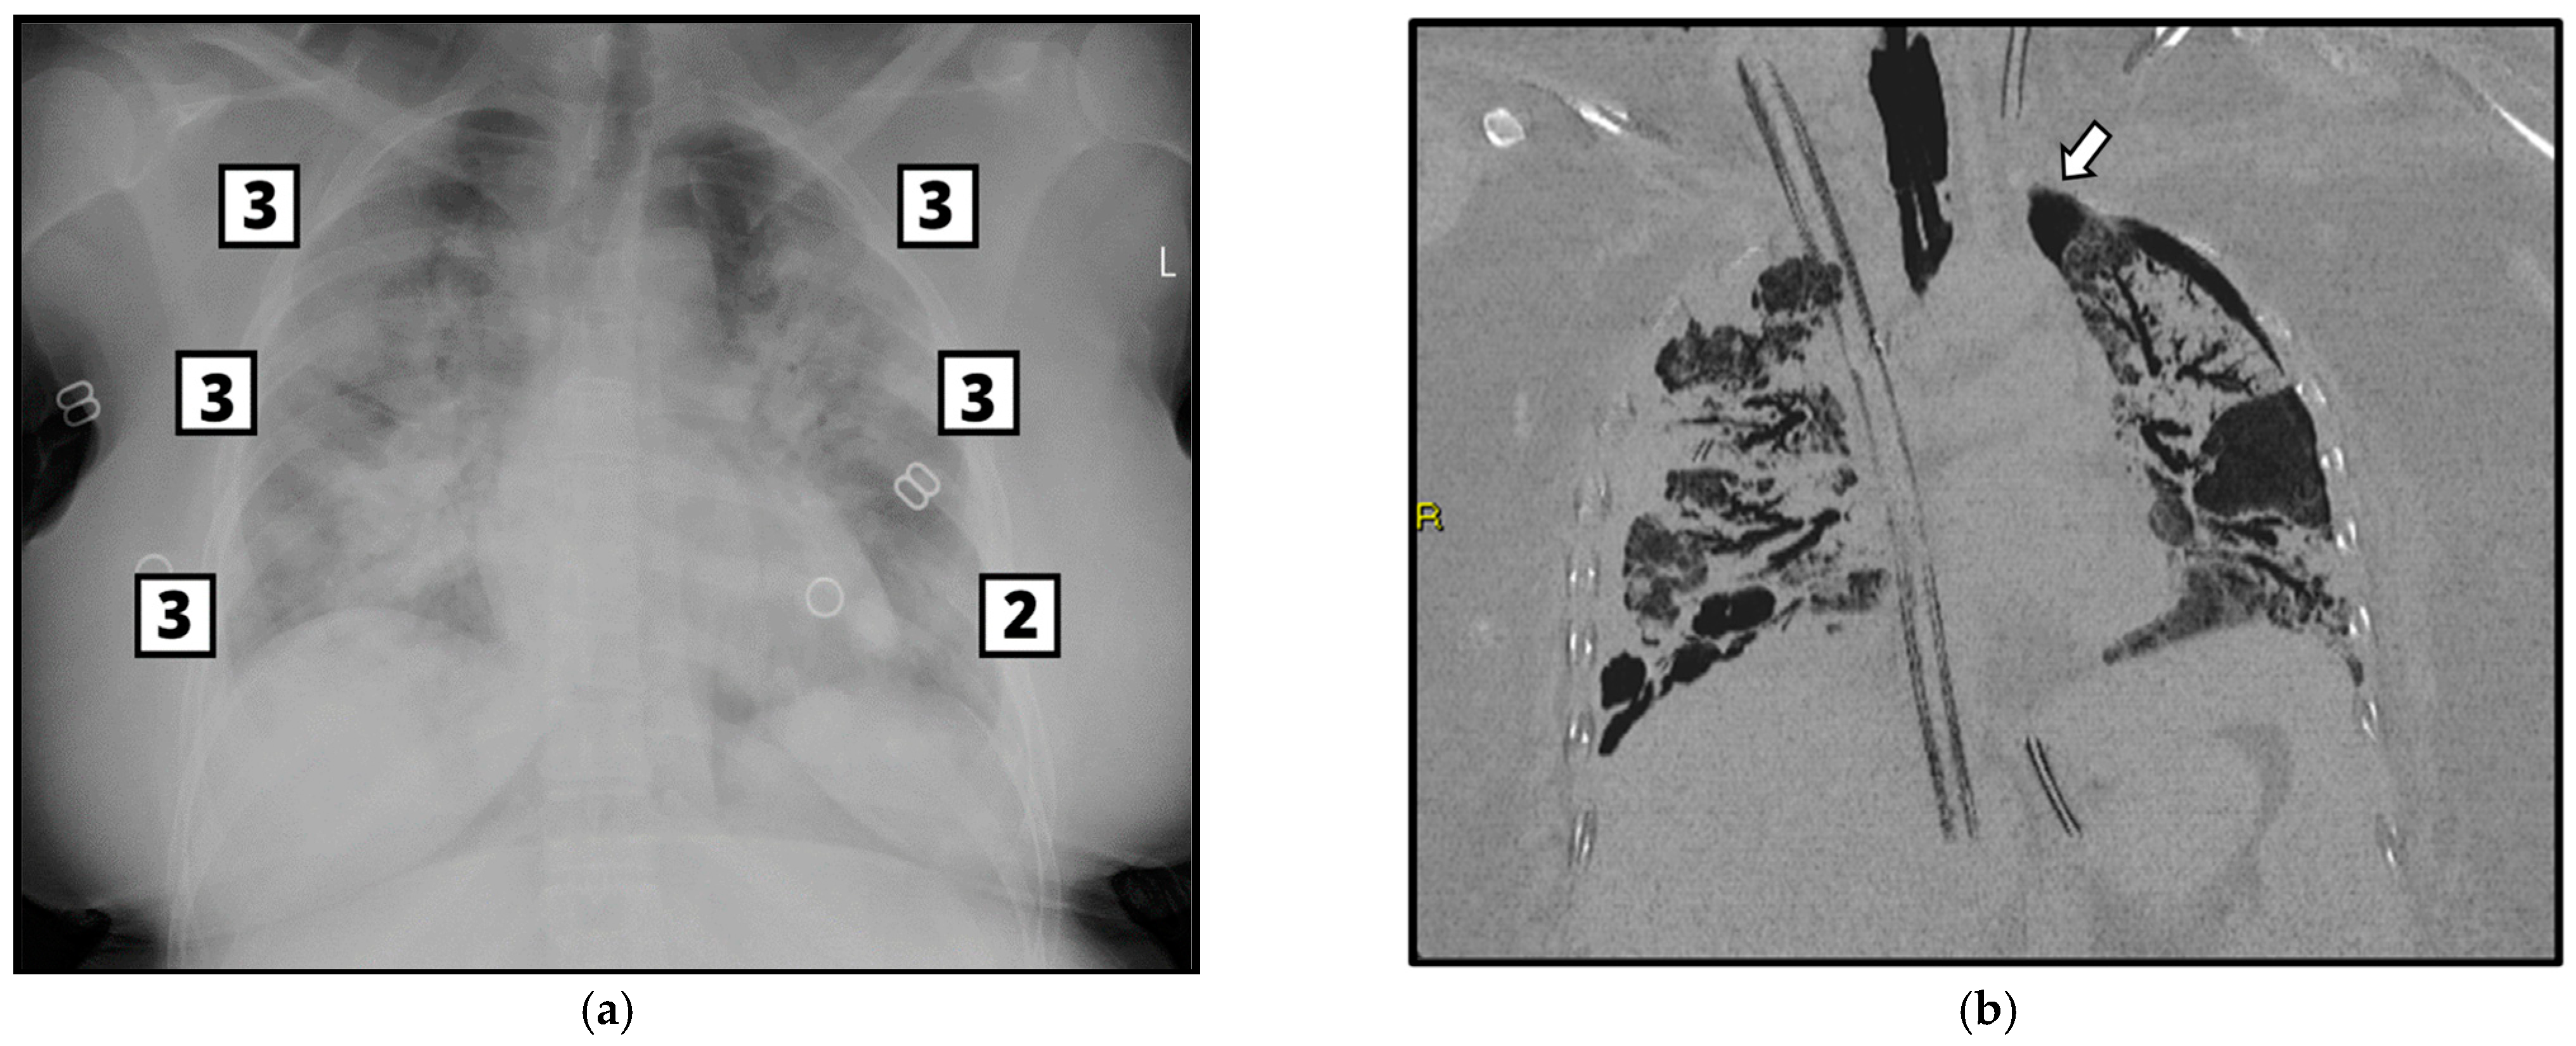

2.3. Imaging Acquisition and Analysis—CXR and CT

3.3. Brixia Score